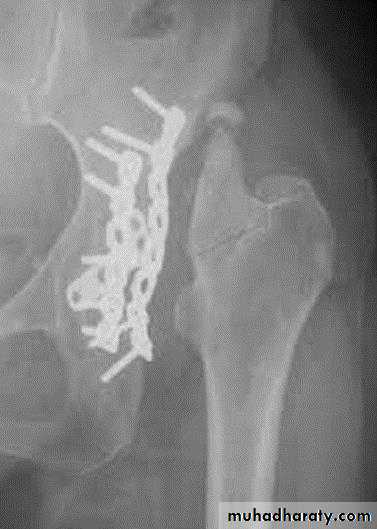

open reduction and internal fixationindications

physiologically stable

no local infection

pregnancy is not contraindication to surgical fixation

displacement of roof (> 2 mm)

intra-articular loose bodies

irreducible fracture-dislocation